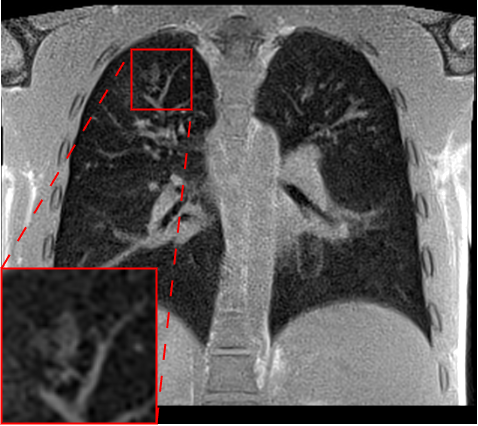

Table 2 and Fig. 4 provide a comparative evaluation of the models on airway lesions segmentations using the Holistic Airway Lesions (HAL) pipeline with Dice score and NSD. Models leveraging the AFP loss using HAL’s embeddings provide the best performances. Specifically, for bronchiectasis, the model using HAL’s embeddings achieves an NSD of 0.516, significantly outperforming the L1 loss model which only reaches 0.373. Additionally, the model with AFP loss using only NaviAirway’s embeddings also shows strong results, while other models are generally of poor quality on this task.

| Loss | Bronchiectasis | Bronchial Mucus | ||

| Dice | NSD | Dice | NSD | |

| L1 | ||||

| Perceptual | ||||

| AFP TotalSeg | ||||

| AFP Navi | ||||

| AFP HAL | ||||

| AFP Navi + HAL | ||||

Note: *Indicates statistical significance compared to L1 loss, as measured using the Wilcoxon signed-rank test. P values less than 0.05 were considered statistically significant.